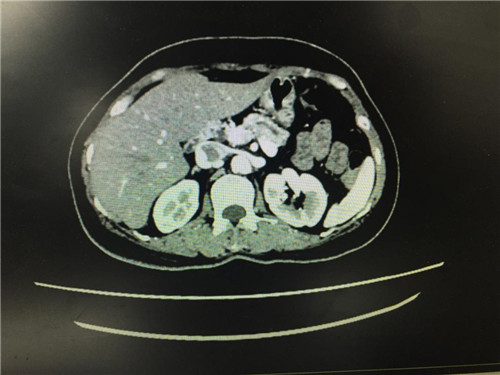

2月12日,普外科收治了一名女性患者,该患者入院一个月前,无明显诱因出现上腹部疼痛不适,呈间断性,向腰背部放射,有恶心,无呕吐,近一个月体重下降了5kg。门诊查上腹部CT提示:胰颈部新生物并胰管扩张;副脾。

患者病情复杂,在潘承恩教授和全科医生的讨论下,结合检验及检查结果,术前胰腺颈体部肿瘤诊断明确,科室积极制定手术方案,详细向家属探明病情并取得合作。2月21日,由普外科史和平主任、梁鹏锋医师主刀,在王谦、李垚磊医师配合下,成功对该患者实施了剖腹探查、全胰腺切除、脾脏切除术。手术中发现,患者胰腺颈体部可触及一大小约4cm包块,胰头部质软,胰腺体尾部质硬,遂决定行胰腺颈体尾部切除及脾脏切除术。在胰腺近侧断端切取部分胰腺组织送术中快速冰冻,提示查见异型增生的胰腺腺泡样组织,联系病理科考虑癌细胞残留,术中向家属谈明病情并取得同意,遂行胰十二指肠切除术,手术顺利,术后生命体征平稳,并于术后第四日进行了复查CT结果良好。